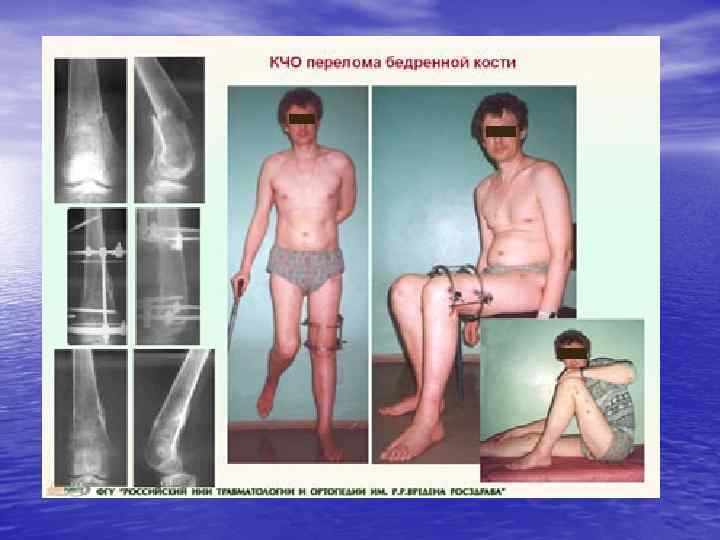

металлостеосинтез

металлостеосинтез

металлостеосинтез

металлостеосинтез

металлостеосинтез

металлостеосинтез

металлостеосинтез

металлостеосинтез

металлостеосинтез

металлостеосинтез

металлостеосинтез

металлостеосинтез